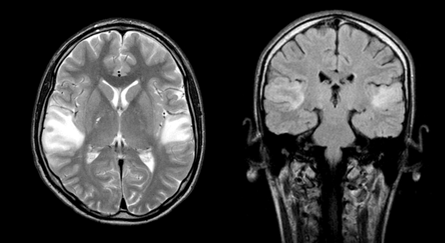

The patient's condition remained stable only for a year. Since April 2012, my eyesight has deteriorated again. MRI of the brain (October 2012) showed a massive scar-atrophic process in both occipital lobes, cortico-subcortical foci of gliosis in the temporal lobes (Figure 6).

Figure 6 MRI of the brain in T2 VI and FLAIR modes (October 2012). A massive cicatricial-atrophic process in both occipital lobes is visualized. Cortico-subcortical foci of gliosis in the temporal lobes.